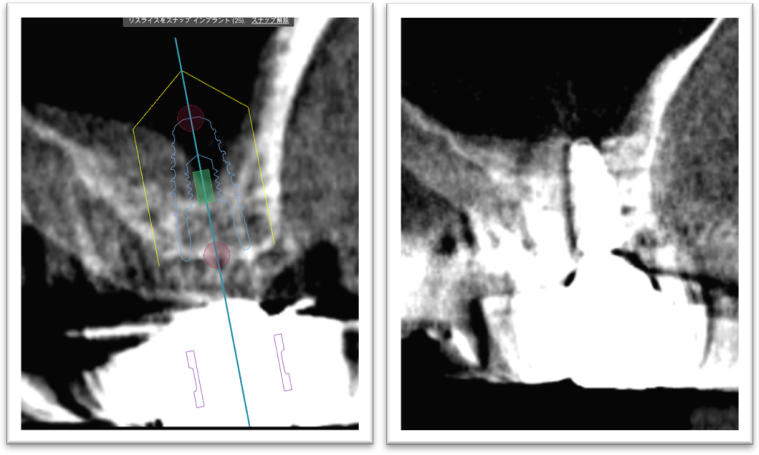

③ガイデッドサージェリーにてインプラント埋入しました。

④計画通りの埋入が出来ました。

レントゲン写真でも理想的な位置

に埋入できました。